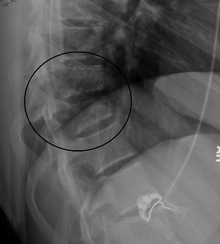

| A chance fracture of T10 and fracture of T9 due to a seatbelt during an MVC. | |

A Chance fracture is a flexion injury of the spine,[1] first described by G. Q. Chance in 1948.[2] It consists of a compression injury to the anterior portion of the vertebral body and a transverse fracture through the posterior elements of the vertebra and the posterior portion of the vertebral body. It is caused by violent forward flexion, causing distraction injury to the posterior elements.

The most common site at which Chance fractures occur is the thoracolumbar junction (T12-L2) and midlumbar region in pediatric population.[3] This fracture initially became known as a "seat belt injury" due to its association with the sudden forward flexion that occurs when one is involved in a head-on automobile collision while being restrained by a lap belt. With the advent of both lap and shoulder belts in the 1980s, Chance fractures have become less common especially now that lap-belt-only seat belts have been almost entirely phased out.